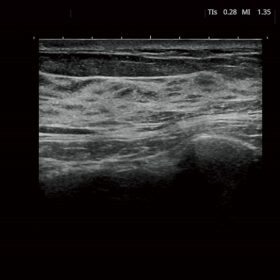

FUTUS features great imaging technologies to support a clear view and confident diagnoses.